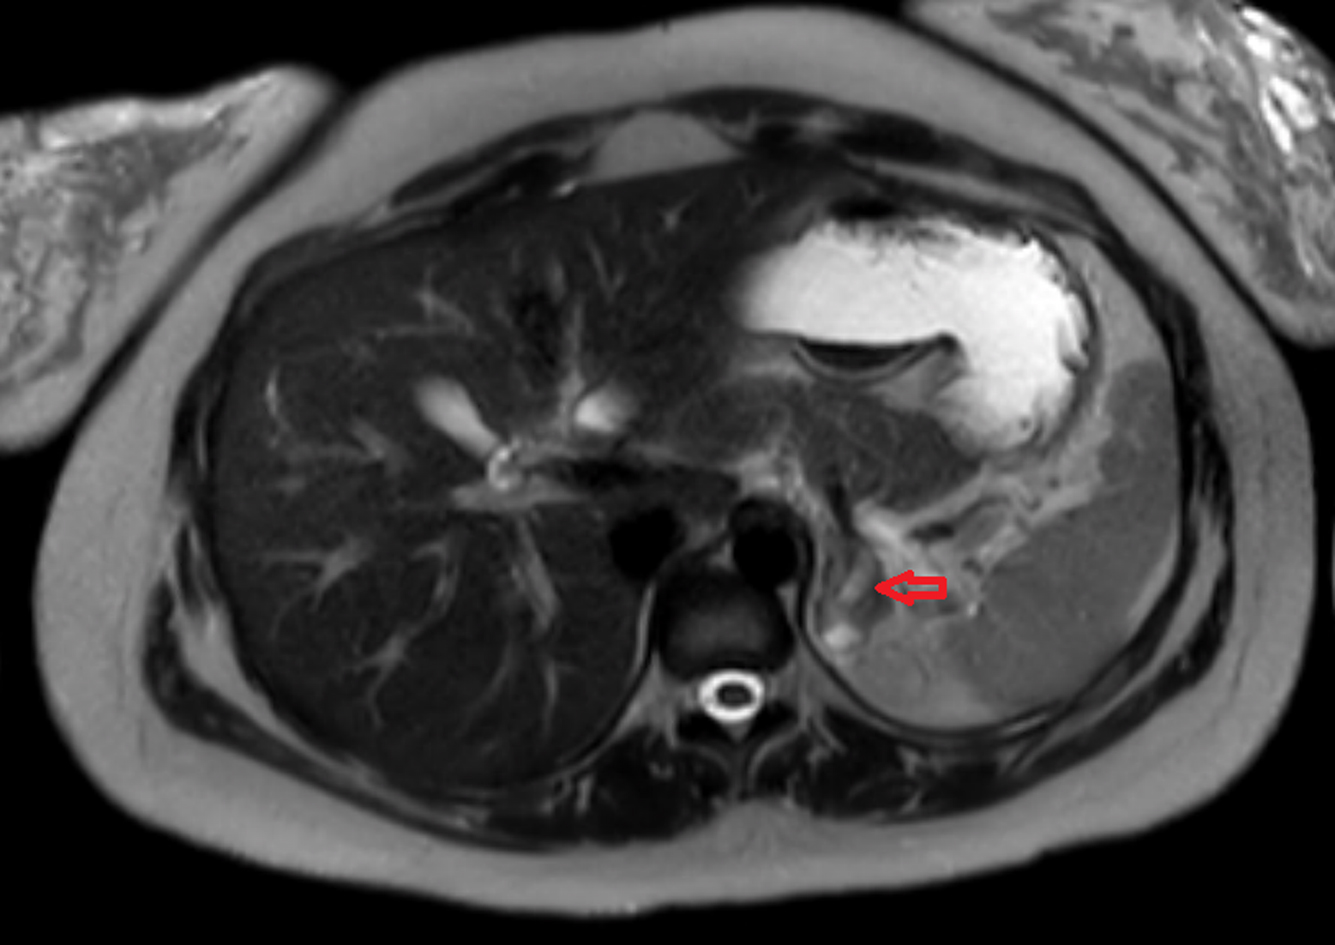

From edm.bioscientifica.com

Newonset primary adrenal insufficiency in pregnancy associated with a Adrenal Insufficiency After Pregnancy Adrenal insufficiency in pregnancy, although relatively rare, has significant clinical implications on both maternal and fetal. In this review, we describe pregnancy induced changes in adrenal function, the diagnosis and management of adrenal insufficiency in. The prevalence of primary adrenal insufficiency (addison’s disease) during. Adrenal crisis in pregnancy is rare and may present like hyperemesis gravidarum. Clinical features, diagnosis and. Adrenal Insufficiency After Pregnancy.

Newonset primary adrenal insufficiency in pregnancy associated with a Adrenal Insufficiency After Pregnancy Adrenal crisis in pregnancy is rare and may present like hyperemesis gravidarum. Appropriate management of adrenal insufficiency (ai) in pregnancy can be challenging. Adrenal insufficiency symptoms overlap with features that might be related to pregnancy itself, such as fatigue,. In this review, we describe pregnancy induced changes in adrenal function, the diagnosis and management of adrenal insufficiency in. Clinical features,. Adrenal Insufficiency After Pregnancy.